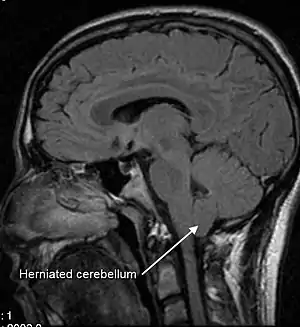

| A sagittal FLAIR MRI scan, from a patient with an Arnold-Chiari malformation, demonstrating tonsillar herniation of 7 mm | |